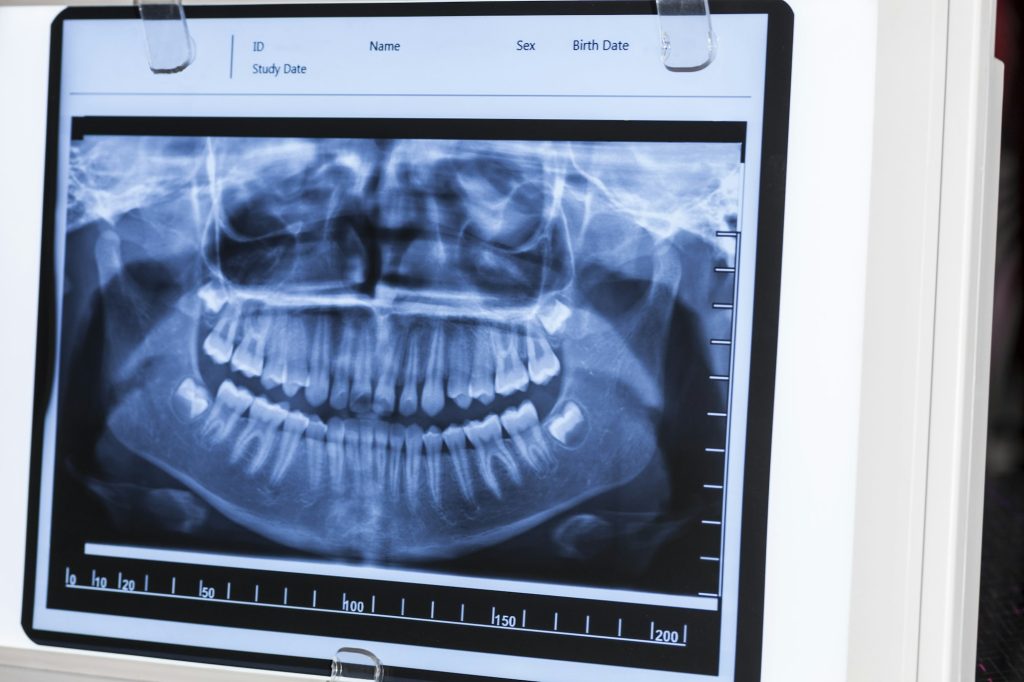

Dental radiology is a specialized field of medical imaging that focuses on the use of X-rays and other imaging modalities to diagnose and treat dental and oral health conditions. Radiologic technologists and dental hygienists play a crucial role in this field, working closely with dentists and other healthcare professionals to provide high-quality imaging services.